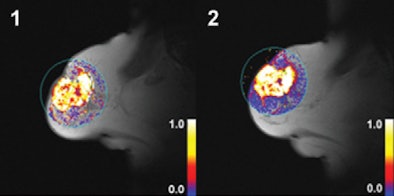

![]() |

| Dynamic T1-weighted MR images of a 60-mm grade 2 breast carcinoma in the right breast of a 70-year-old woman whose disease relapsed 38.8 months after diagnosis. The patient died 47.2 months after initial radical treatment. Her tumor displayed high values for Ktrans after two cycles of chemotherapy. (1) Ktrans before treatment; (2) Ktrans after treatment. Images courtesy of Radiology. |